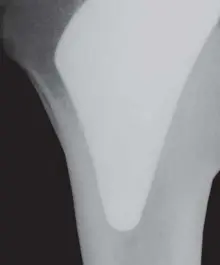

هنا يبرز دور مفصل بروكسيما للورك ، وهو زرعة مبتكرة لا تحتوي على جذع (stemless) وتتركز في منطقة الميتافيزيال (metaphyseal) من عظم الفخذ. تم تصميم هذا المفصل ليحمل الحمل قربياً، أي في الجزء العلوي من عظم الفخذ، مما يحاكي التحميل الفسيولوجي الطبيعي للعظم. يساهم هذا التصميم في الحفاظ على العظم بطريقتين: الأولى، بتقليل ظاهرة "حماية الإجهاد" التي تسبب ضعف العظم، والثانية، بالسماح بإجراء جراحات مراجعة مستقبلية (إذا لزم الأمر) بطريقة أسهل وأقل تعقيداً، حيث يتم الحفاظ على مخزون عظمي أكبر.

• التثبيت في المنطقة الميتافيزيال (Metaphyseal Fixation): بدلاً من التثبيت في الجزء الأوسط من عظم الفخذ (الديافيزيس)، يتم تثبيت مفصل بروكسيما في المنطقة الميتافيزيال، وهي المنطقة القريبة من رأس عظم الفخذ. هذه المنطقة تتميز بكثافة عظمية عالية وقدرة ممتازة على الاندماج العظمي.

• التحميل القريب (Proximal Loading): يحاكي تصميم بروكسيما الطريقة الطبيعية التي ينتقل بها الحمل عبر عظم الفخذ. من خلال تركيز توزيع الضغط في الجزء العلوي القريب من العظم، يتم تحفيز العظم للحفاظ على كثافته وقوته.

• تقليل "حماية الإجهاد" (Stress Shielding): في الزرعات التقليدية ذات الجذع الطويل، تنتقل معظم قوى الوزن والضغط إلى الجذع المعدني بدلاً من العظم المحيط به. هذا يقلل من الإجهاد الميكانيكي على العظم، مما يؤدي إلى "حماية الإجهاد"، وهي ظاهرة تؤدي إلى امتصاص العظم (Bone Resorption) وضعفه بمرور الوقت. مفصل بروكسيما، بتصميمه الذي يحمل الحمل قربياً، يقلل بشكل كبير من هذه الظاهرة، مما يحافظ على صحة العظم المحيط.